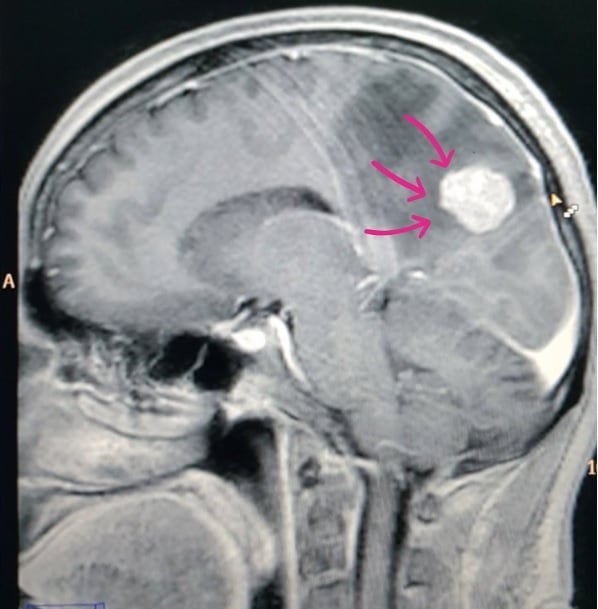

A ressonância magnética (RM) com contraste gadolínio é o exame padrão-ouro, detectando lesões pequenas e diferenciando metástases de outras condições. Em emergências, a tomografia computadorizada (TC) com contraste é usada inicialmente.

Se o tumor primário for desconhecido, biópsia cerebral (cirúrgica ou estereotáxica) confirma o diagnóstico e permite análise molecular para terapias direcionadas.